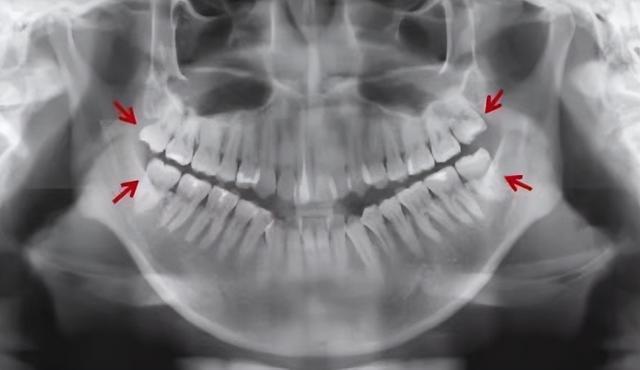

智齿是否需要拔掉,首先需到专业的口腔科进行口腔检查并配合医生完成口腔X线片的检查,根据智齿的生长方向以及与周围组织的位置关系来决定。

1. 如果智齿垂直向完全萌出,且与前面牙齿邻接关系良好,对牙合的智齿也已经萌出,上下颌的咬合关系比较正常,牙周组织健康,一般不用拔掉。

(▲上下颌智齿正位萌出)

2.如果智齿没有完全萌出,牙龈覆盖较多,导致患者经常红肿化脓,则需要拔掉。

3.如果智齿倾斜,牙冠直接抵到前面牙齿的牙根或牙颈部部位,也需要拔掉。